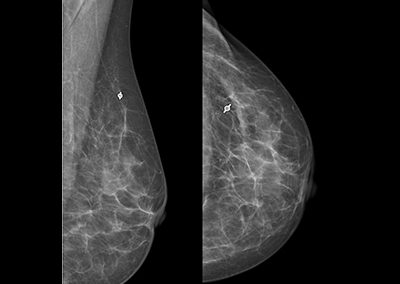

Case 4, fig. 3

Mammography left ML (left image) and CC (right image) two months after marking following two NACT cycles. Finding cannot be clearly differentiated (anymore), marker within the tumor bed.